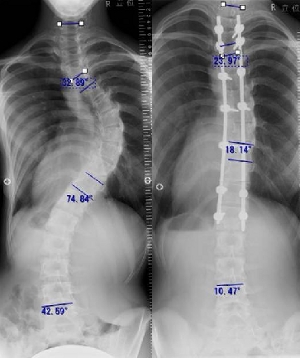

第14回 側弯症の矯正固定術脊椎手術.com。